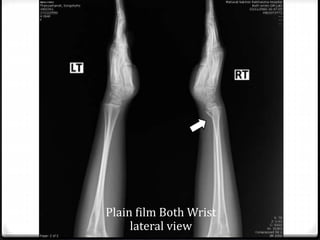

0 Plain film Both Wrist AP , lateral view

Plain film Both Wrist

lateral view

0 Closed fracture of Rt. distal end radius with

Epiphyseal plate injury ( Salter-Harris II )